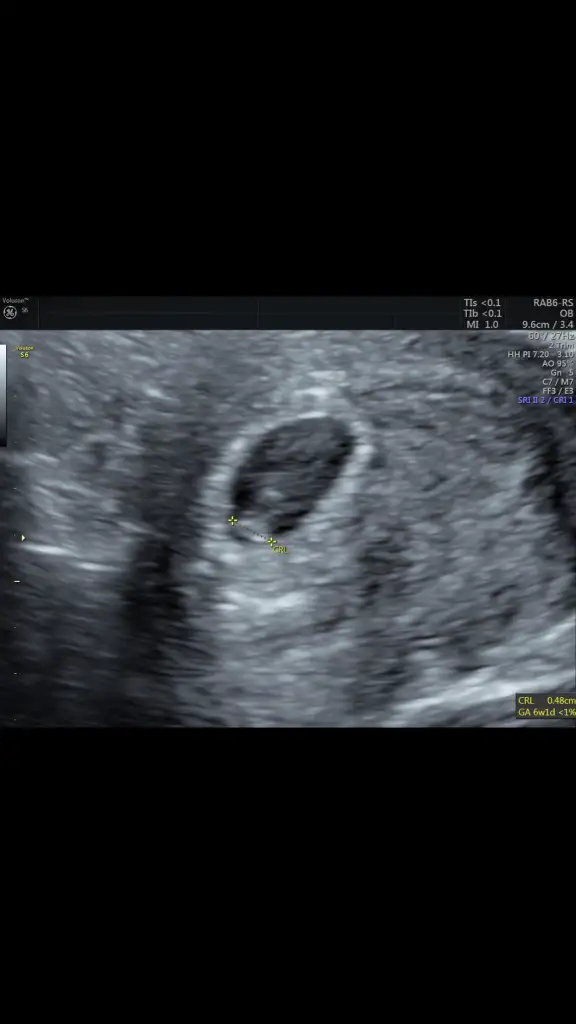

Merhaba başka sayfaya da yollamıstım ama komse bakmadı 6. Hafta vajinal ultrasonum paylasıyorum. Bırısı yorumlarsa sevınırım şuan artık 11. Haftam oldu